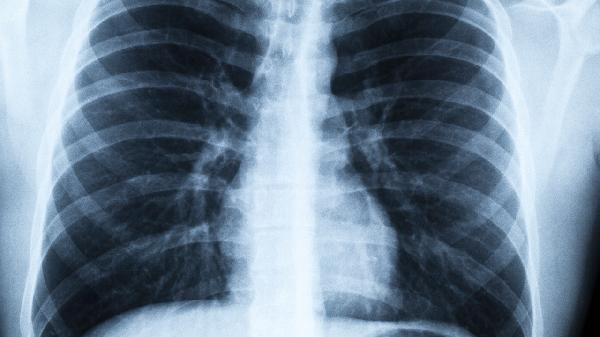

甲型和乙型流感病毒是成人病毒性肺炎的常见病因。病毒通过血凝素蛋白与呼吸道上皮细胞结合,导致细胞坏死和炎症反应。临床特征包括突发高热、肌痛等全身症状,胸部CT可见多肺叶磨玻璃影。糖尿病患者和孕妇感染后易出现急性呼吸窘迫综合征。